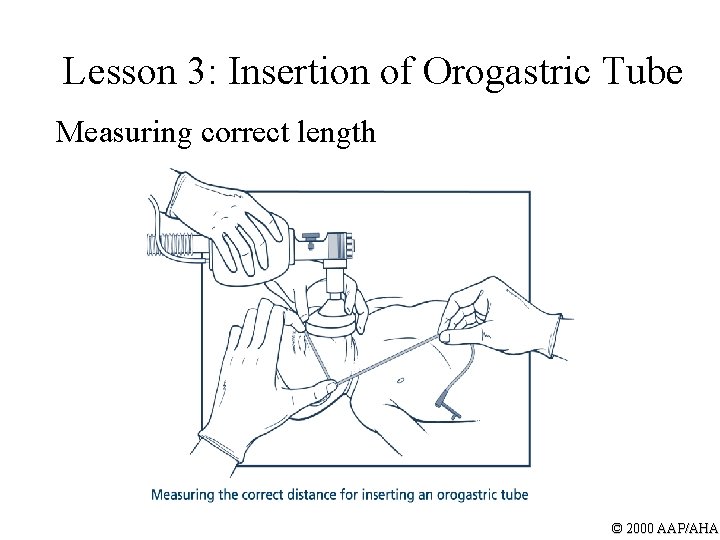

Lesson 3: Insertion of Orogastric Tube Measuring correct length © 2000 AAP/AHA